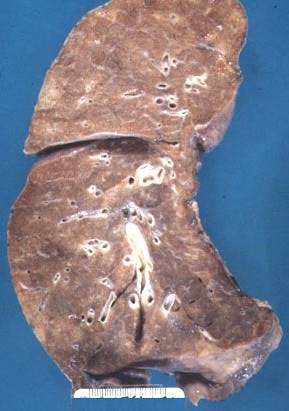

Cut surface of normal lung.